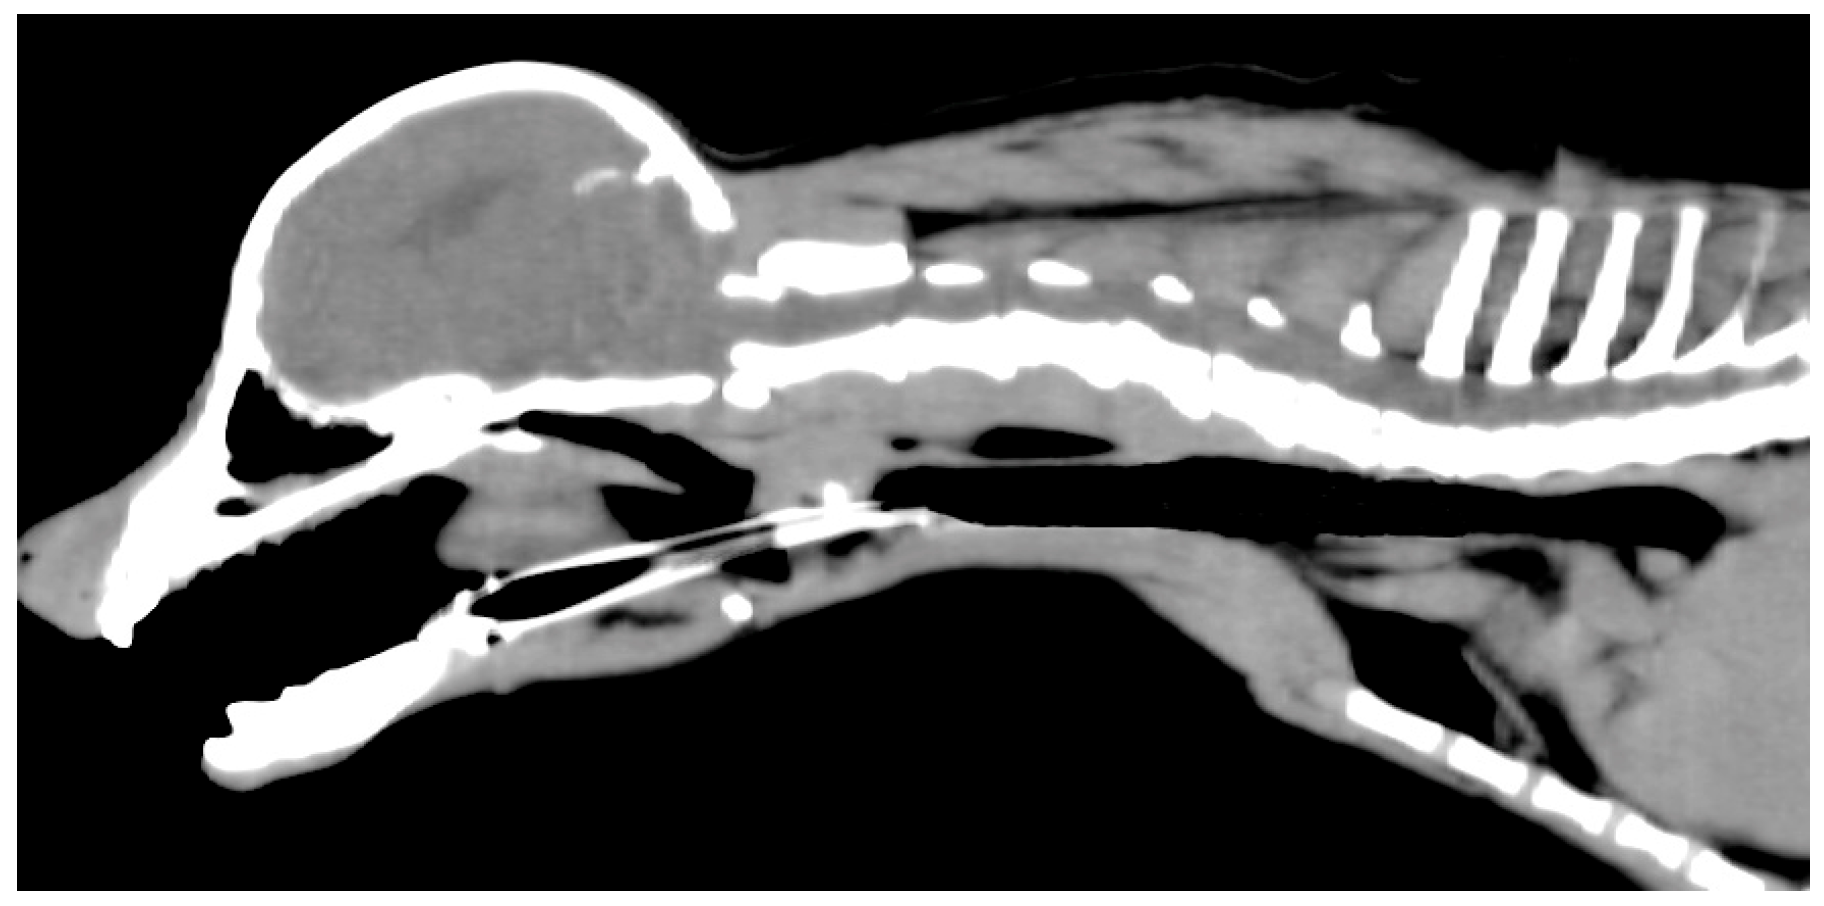

Based on Computed Tomography (CT), the stent diameter was chosen to be 10–20% larger than the maximum diameter of the caudal trachea without collapse [14,15] (Figure 2). Although the stent length covered the entire trachea, it was selected so that the cranial end would not contact the larynx and the caudal end would not contact the tracheal carina [6,8,15]. A 10 mm diameter, 80 mm long, a Nitinol cross-and-hook braided self-expanding metal stent (Fauna Stent; M.I. Tech Co., Ltd., Seoul, Republic of Korea) was selected.

Figure 2. Computed tomography images of the dog. Based on these images, the maximum diameter of the caudal trachea without collapse was estimated to be approximately 9 mm. The stent length was selected so that the cranial end would not contact the larynx and the caudal end would not contact the tracheal carina.